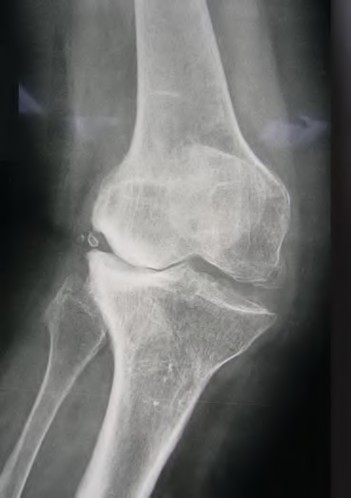

A 55-year-old male presents with isolated medial compartment osteoarthritis of the right knee. He is being evaluated for a medial unicompartmental knee arthroplasty (UKA). Which of the following physical examination or radiographic findings is an absolute contraindication to a medial UKA?

According to the classification of cementless femoral stems, a fully porous-coated cylindrical stem relies on which area for its primary mechanical fixation?

During a revision total knee arthroplasty, removal of the tibial component reveals a massive contained metaphyseal defect measuring 3 cm deep, but with an intact cortical rim. According to the Anderson Orthopaedic Research Institute (AORI) classification, what type of defect is this, and what is the preferred method of management?

Which of the following is traditionally considered an absolute contraindication to a medial mobile-bearing unicompartmental knee arthroplasty (UKA)?

When evaluating a patient for a Unicompartmental Knee Arthroplasty (UKA), which of the following is considered a classic absolute contraindication?